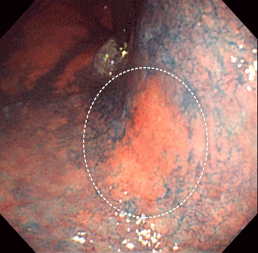

通常の観察では、わずかに発赤しているのみです。

NBIという特殊光モードにすることで、コントラストがはっきりします。

バレット上皮という状態から発生した腺がんです。

類基底細胞がんという特殊なタイプのがんでした。